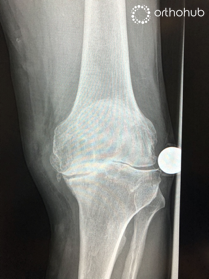

AP and Lateral radiographs

77 year old lady in severe pain in her knee. She had a previous open lateral meniscectomy at age 20, and a further open procedure for 'problems with her knee cap' 30 years ago.

On examination she has a clinical valgus deformity, and an elevated BMI.